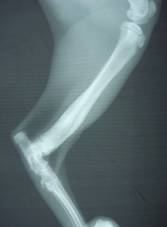

約2ヶ月後のレントゲン写真。

骨折部は完全に癒合している。

現在は、肢の状態は全く問題ないようである。